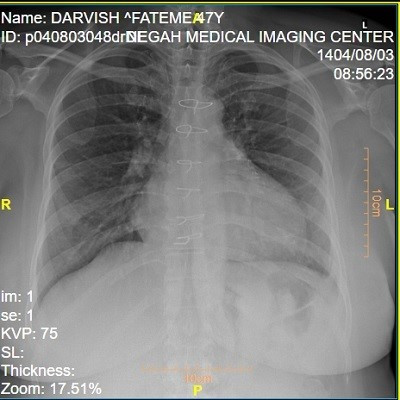

در برخی از بیماران ، از روش هایی مانند رادیولوژی بلع باریم استفاده می شود در این تست ، بیمار ماده حاجب می نوشد و سپس با تصویر برداری اشعه ایکس ، شکل و حرکت مری بررسی می شود. این روش بیشتر برای تشخیص تنگی مری یا اختلالات حرکتی کاربرد دارد و معمولا به عنوان مکمل آندوسکوپی استفاده می گردد. همچنین در موارد خاص ، اندازه گیری اسید مری برای بررسی شدت رفلاکس اسید انجام می شود.